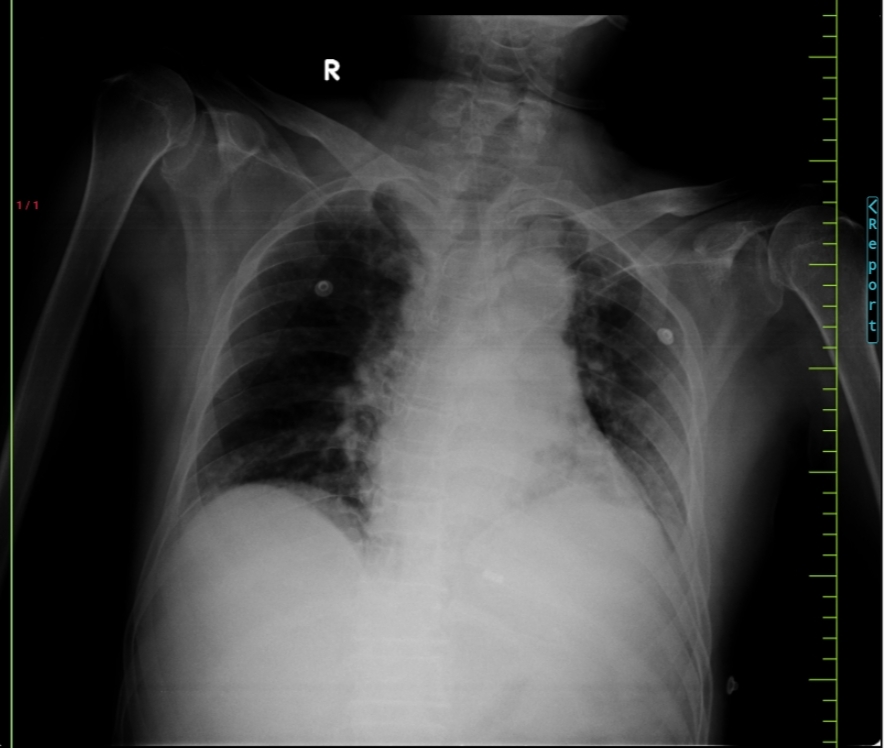

Chest X-Ray

Chest xray - 29.6.23

Chest X-Ray - 1/7/23